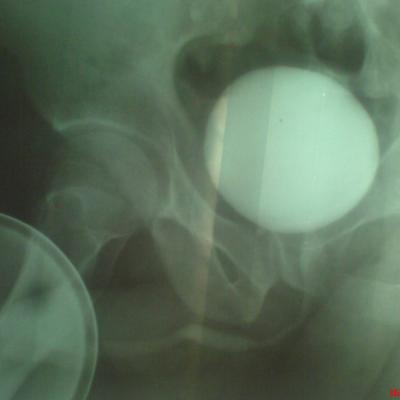

Возможно у Вас проконсультироваться таким образом,я вышлю Вам снимки уретрограмм а Вы скажете свое мнение.